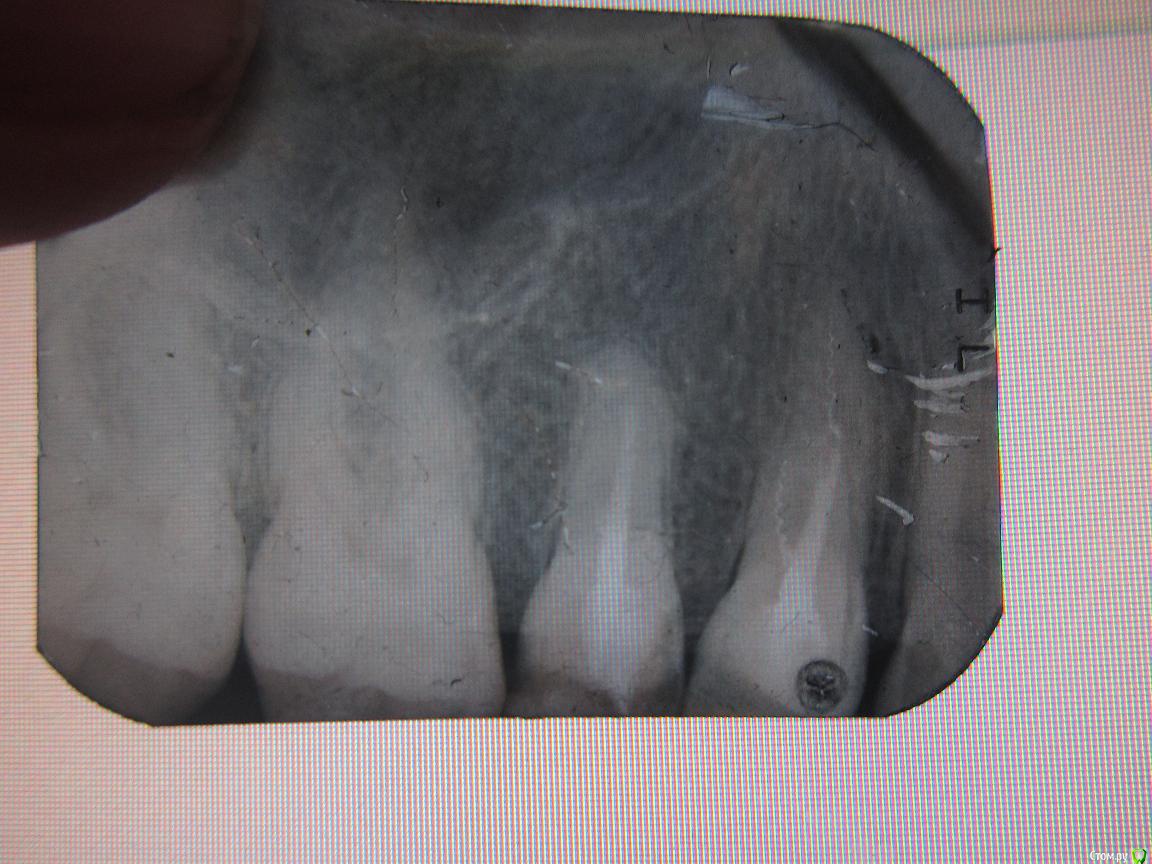

мухит Опубликовано 2 июня, 2015 Поделиться Опубликовано 2 июня, 2015 (изменено) Пломбировал два зуба с разницей в год ,( один месяц назад) Зуб начал беспокоить , пошел к другому стамотологу , он сказал надо удалять два зуба т.к воспаление корня. Действительно ли нет выхода или стоит обратиться в область? На фото 2 зуба справа ( а так они 14 .15). Второй стоматолог сказал что зубы вылечены не до конца. И второй вопрос у меня уже 5 кариес за два месяца. Связано ли это что я пол года назад переехал в другую страну? Изменено 2 июня, 2015 пользователем мухит Ссылка на комментарий

мухит Опубликовано 3 июня, 2015 Автор Поделиться Опубликовано 3 июня, 2015 Удалять не нужно. Нужен грамотный терапевт с микроскопом и тогда есть хорошие шансы на излечение обоих зубов + 1 перелечить и протезировать нет, скорее всего проглядели Каналонаполнители.Не вижу проблемы. Спасибо всем, а вот там на снимке на одном из зубов какая то спираль, она там не будет гнить? Ссылка на комментарий

anvladd Опубликовано 3 июня, 2015 Поделиться Опубликовано 3 июня, 2015 Это каналонаполнитель и его нужно и можно вытащить. 1 Ссылка на комментарий